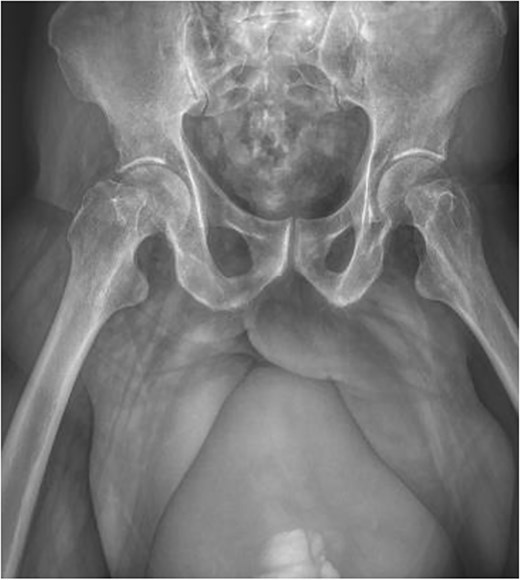

Imaging tests were performed, including a simple anteroposterior pelvic radiograph which showed a composite image with a radiopaque image in the inguinal region continuing caudally with well-defined, regular edges (Fig. 2).